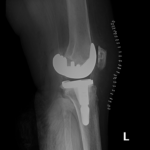

Your doctor will diagnose osteoarthritis based on the medical history, physical examination, and X-rays.

X-rays typically show a narrowing of the joint space in the arthritic knee.

The surgery is performed under spinal or general anesthesia. Your surgeon will make an incision in the skin over the affected knee to expose the knee joint. Then the damaged portions of the femur bone are cut at appropriate angles using specialized jigs. The femoral component is attached to the end of the femur with or without bone cement. The surgeon then cuts or shaves the damaged area of the tibia (shinbone) and the cartilage. This removes the deformed part of the bone and any bony growths, as well as creates a smooth surface on which the implants can be attached. Next, the tibial component is secured to the end of the bone with bone cement or screws. Your surgeon will place a plastic piece called an articular surface between the implants to provide a smooth gliding surface for movement. This plastic insert will support the body’s weight and allow the femur to move over the tibia, similar to the original meniscus cartilage. The femur and the tibia with the new components are then put together to form the new knee joint. To make sure the patella (knee cap) glides smoothly over the new artificial knee, its rear surface is also prepared to receive a plastic component. With all the new components in place, the knee joint is tested through its range of motion. The entire joint is then irrigated and cleaned with a sterile solution. The incision is carefully closed, drains are inserted and a sterile dressing is placed over the incision.